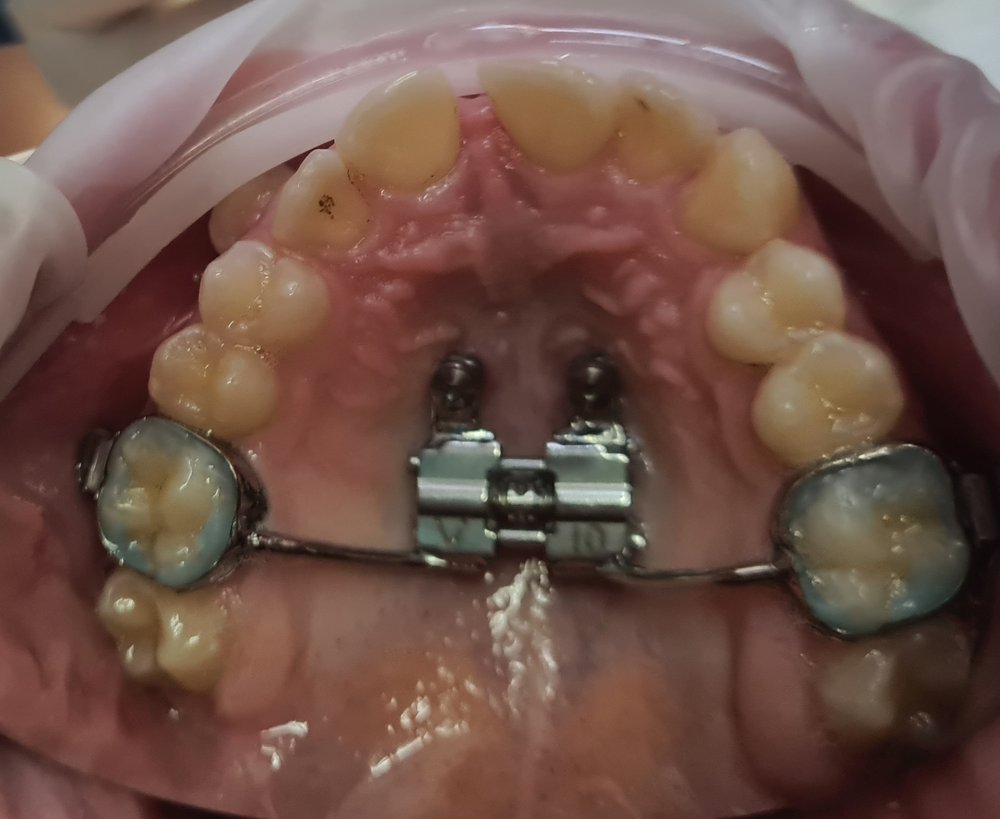

Disjunctoare

Folosirea unui disjunctor maxilar este indicata la copiii la care procesul de crestere a oaselor nu este inca finalizat, si care au maxilare mici, inguste, dinti inghesuiti pe arcada superioara, ocluzie incrucisata sau probleme respiratorii.

Disjunctoare hibride

Disjunctor ancorat pe miniimplanturi.

Este utilizat in cazurile nechirurgicale si non-extractionale pentru marirea maxilarului superior.